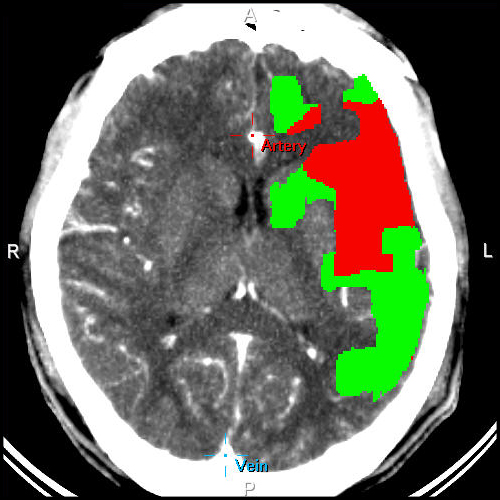

• Différencie les zones de nécrose des zones de pénombre

Cartes pronostique couleurs

Différencie les zones de nécrose des zones de pénombre